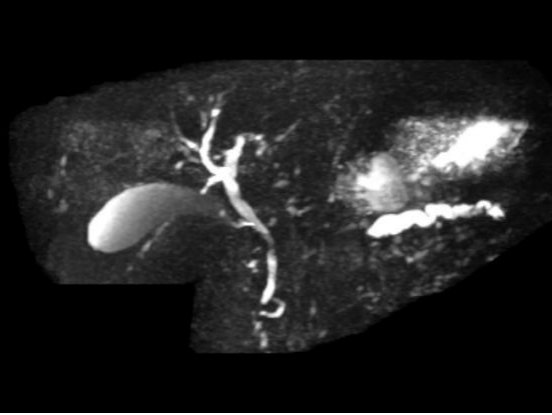

图5A

图5B

典型病例5:

男,60岁,上腹痛。图A:增强T1WI示胰头部团块状弱强化病灶。图B:MRCP示低位胆道梗阻征象,可见肝内外胆管扩张,胆总管扩张,胆囊增大,胰管扩张。